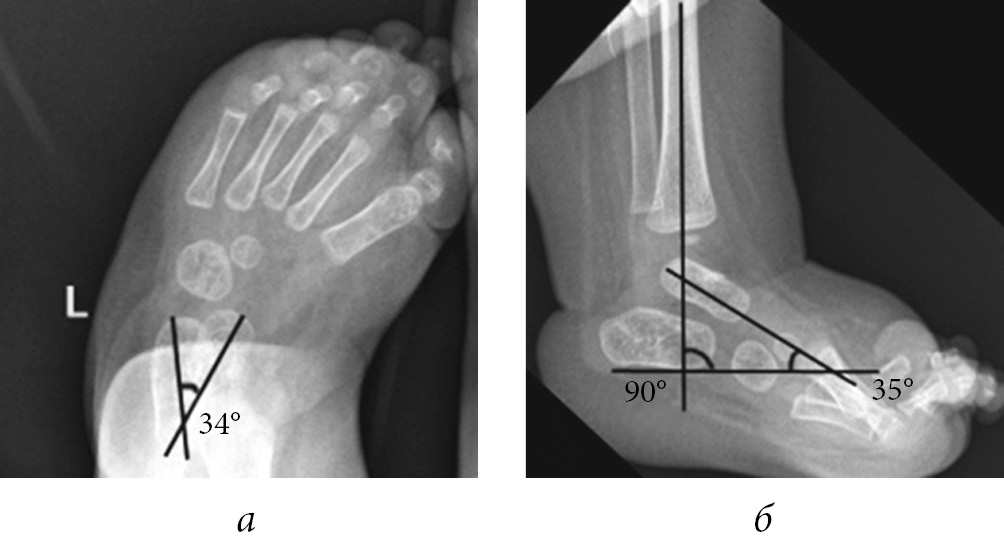

Radiography of the feet was performed in all pediatric patients before and after achillotomy and after plaster cast removal, in two standard views, namely, antero-posterior and lateral in the position of maximum dorsal flexion. After achillotomy, radiography of the feet was performed in a plaster cast immediately after manipulation. Radiographs were analyzed by evaluating the astragalocalcanean angle and astragalocalcanean and calcaneotibial angles in the antero-posterior and lateral views, respectively (Fig. 1).

Fig. 1. Radiograph of the foot of a 5-month-old infant: a — antero-posterior view: astragalocalcanean angle of 34°; b — lateral view: calcaneotibial angle of 90° and astragalocalcanean angle of 35°